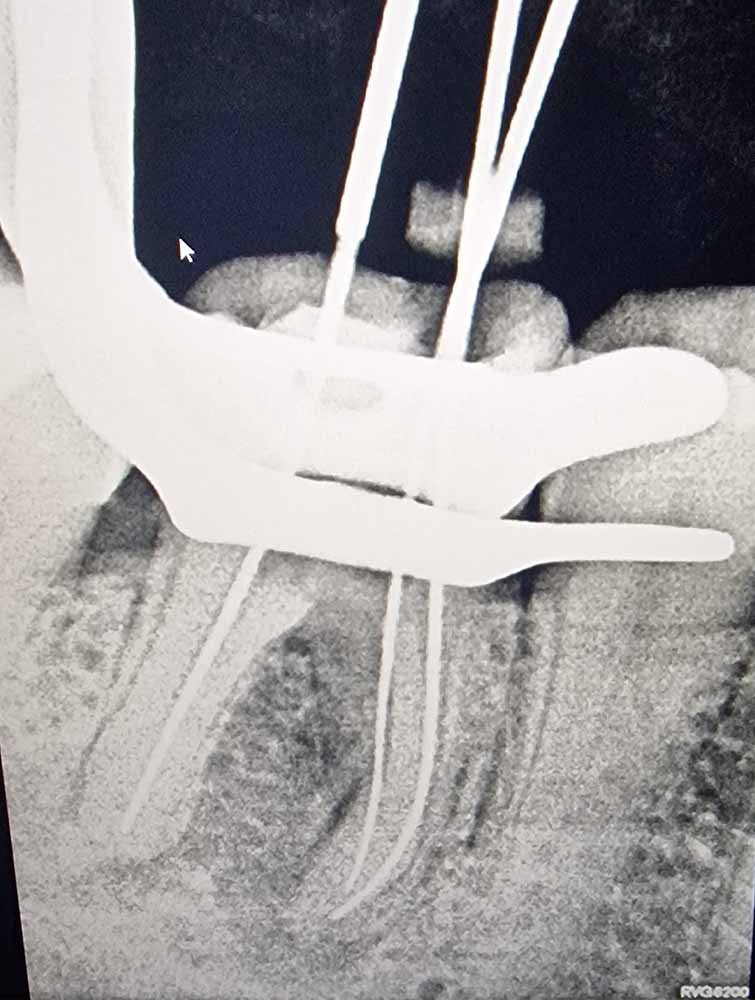

Ακολουθώντας τις πιο σύγχρονες τεχνολογικές εξελίξεις, έχουμε ενσωματώσει προηγμένα εργαλεία και μεθόδους στην ενδοδοντική θεραπεία. Χρησιμοποιούμε περιστροφικά εργαλεία τελευταίας γενιάς, σύγχρονα συστήματα έμφραξης με θερμοπλαστικοποιημένη γουταπέρκα, καθώς και ακριβείς συσκευές ανεύρεσης του μήκους των ριζικών σωλήνων, όπως το apex locator. Επιπλέον, η κλινική μας διαθέτει ψηφιακή ακτινογραφία και CBCT (αξονική τομογραφία) για την ακριβή διάγνωση και τον βέλτιστο σχεδιασμό της θεραπείας.

Ο συνδυασμός της τεχνολογίας με τη λεπτομερή προσέγγιση και την εξατομικευμένη φροντίδα που προσφέρουμε, μας επιτρέπει να επιτυγχάνουμε άριστα αποτελέσματα ακόμα και στις πιο απαιτητικές περιπτώσεις. Στόχος μας είναι η διάσωση των φυσικών δοντιών, διασφαλίζοντας τη μακροχρόνια υγεία και λειτουργικότητα του στόματος των ασθενών μας.